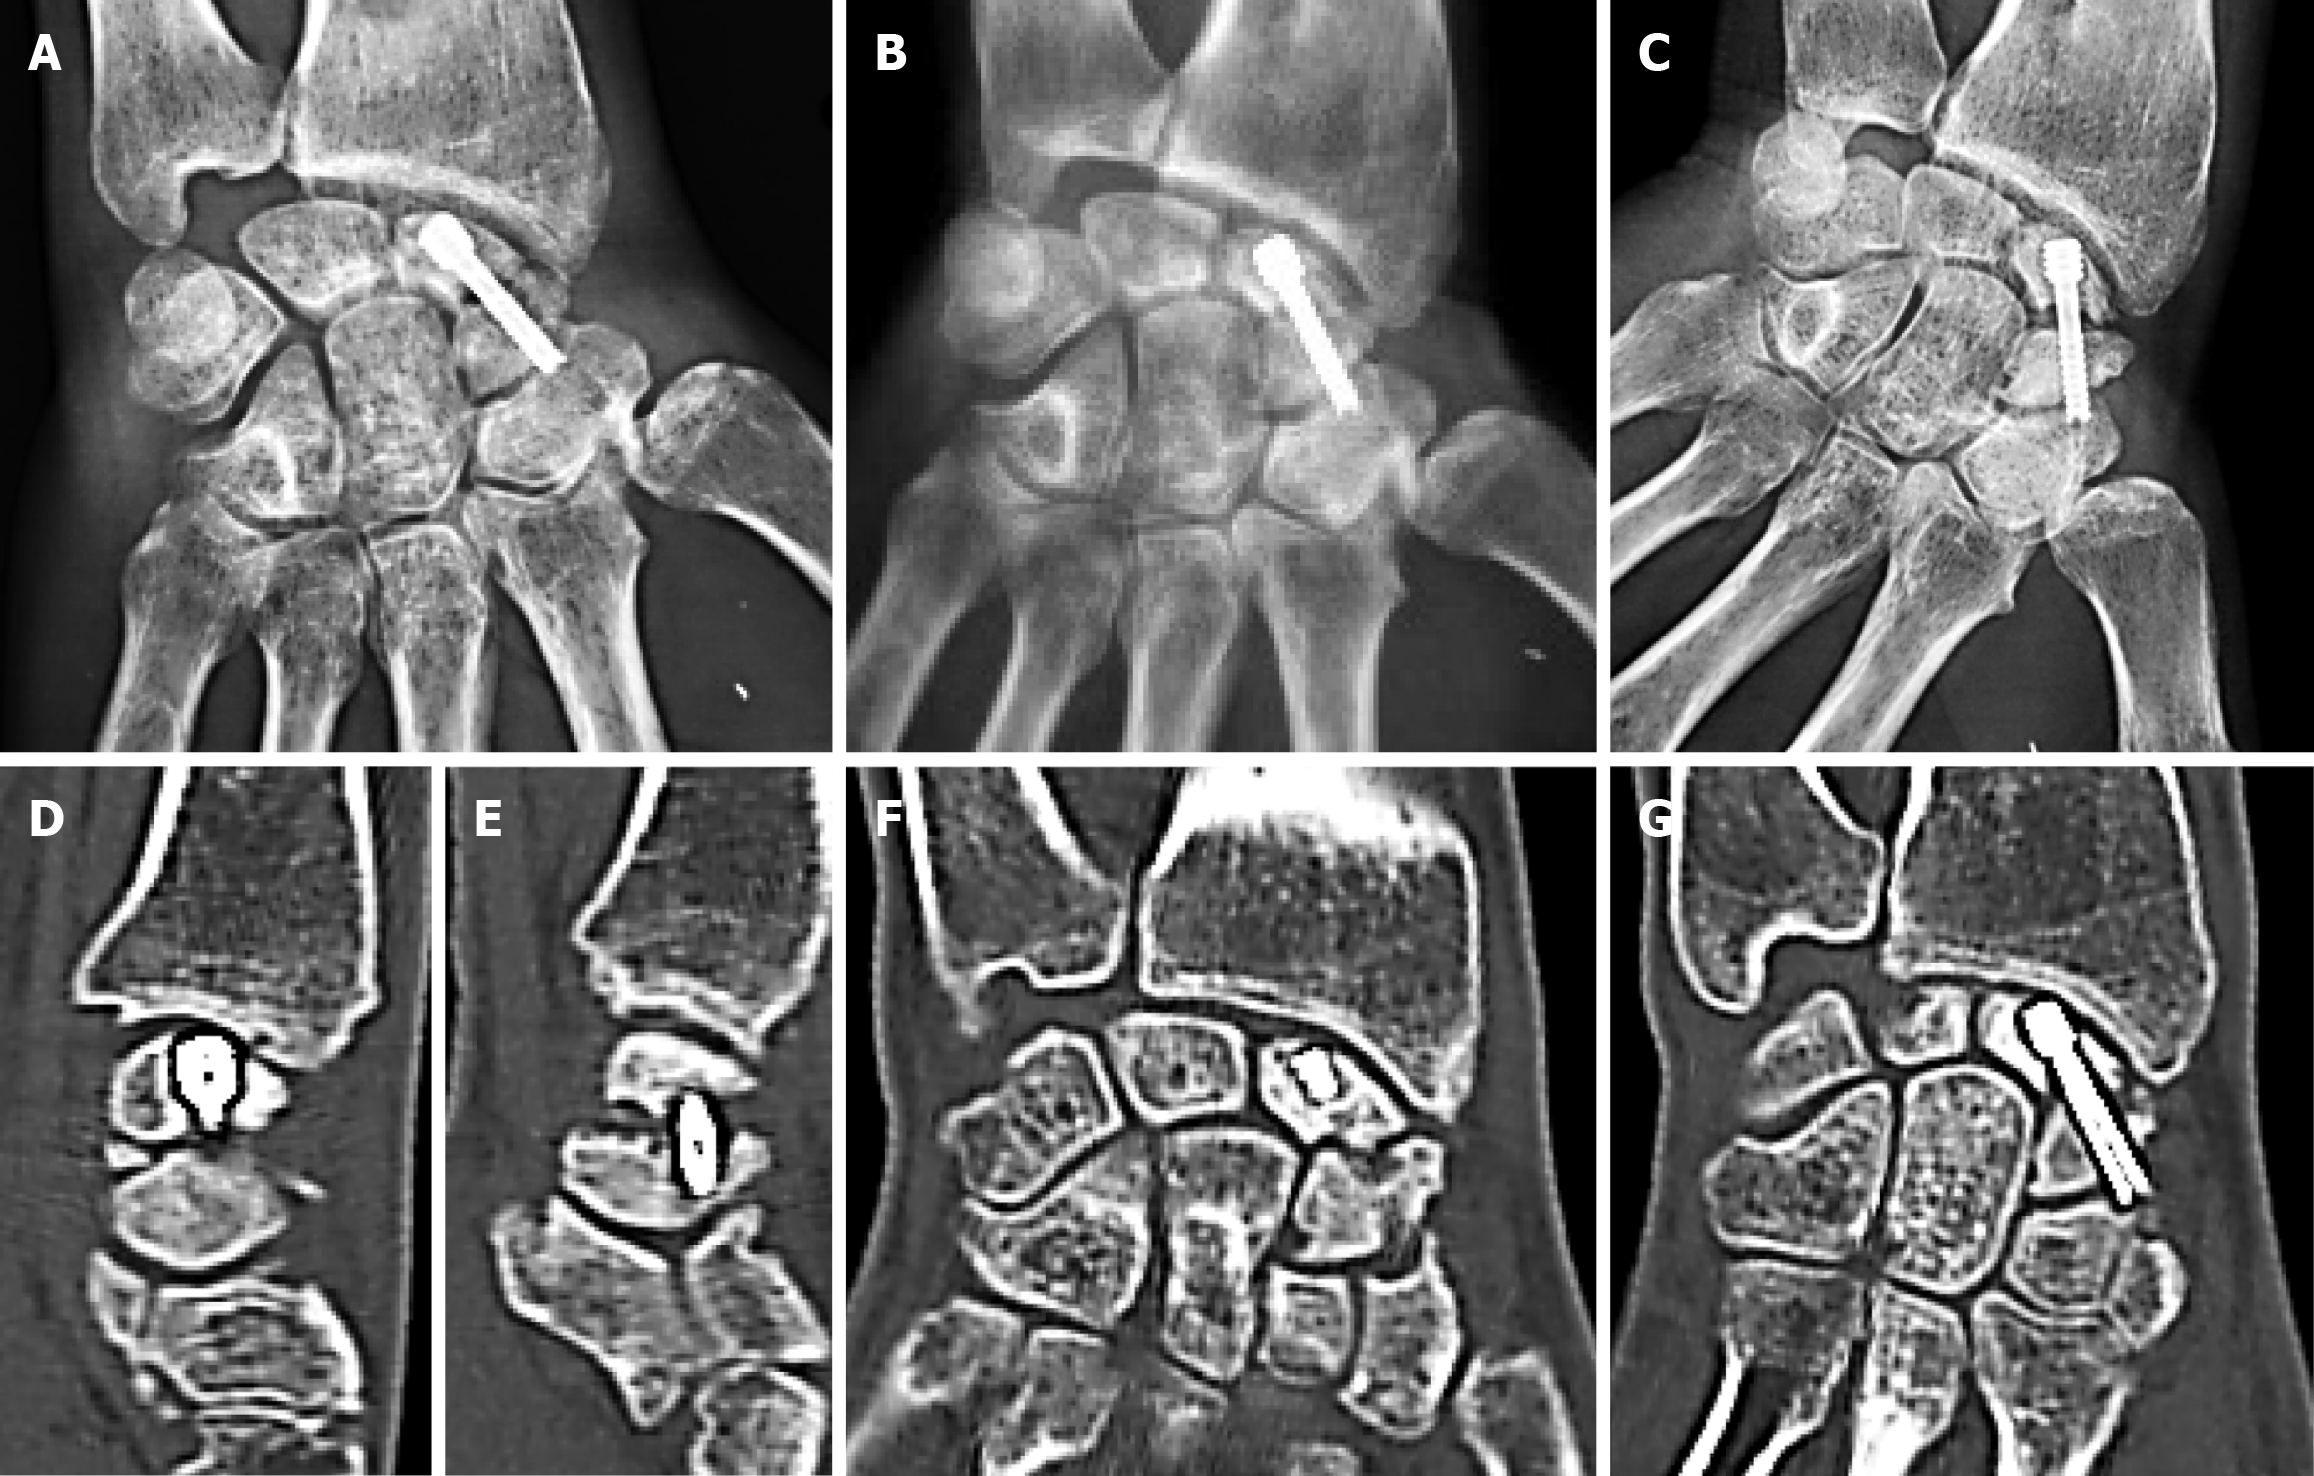

Figure 5 Failure of union after graft-augmented fixation for waist nonunion.

A: Postoperative anteroposterior radiograph one month following fixation of a waist nonunion using cortico-cancellous graft from the iliac crest via the dorsal approach; B: Follow-up radiograph at two months revealing a sunken Herbert screw; C-G: Anteroposterior wrist radiograph and computed tomography slices at eight months showing union failure, graft resorption, and screw penetration into the scapho-trapezial joint.